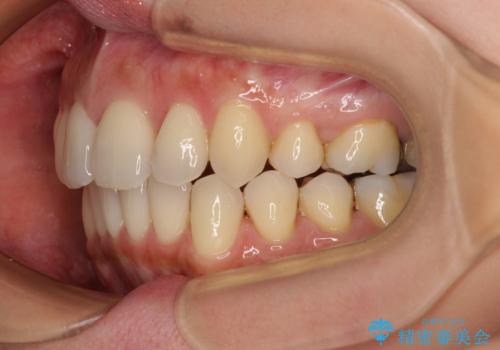

- 上の前歯の突出感を気にして来院された患者様です。

目立たない装置を希望とのことで、上顎左右第一小臼歯を抜歯し、インビザラインにて矯正治療を行うこととしました。

インビザラインにて抜歯矯正を行うと、高頻度で奥歯が咬み合わなくなります。

また、抜歯スペースに向けて奥歯が移動する際、必ず傾斜して移動するため、仕上がりの咬み合わせはワイヤー矯正と比べて明らかに劣ります。

抜歯スペースが閉じてからも咬みにくさ改善のためマウスピース矯正を継続するため、治療期間は長期化します。